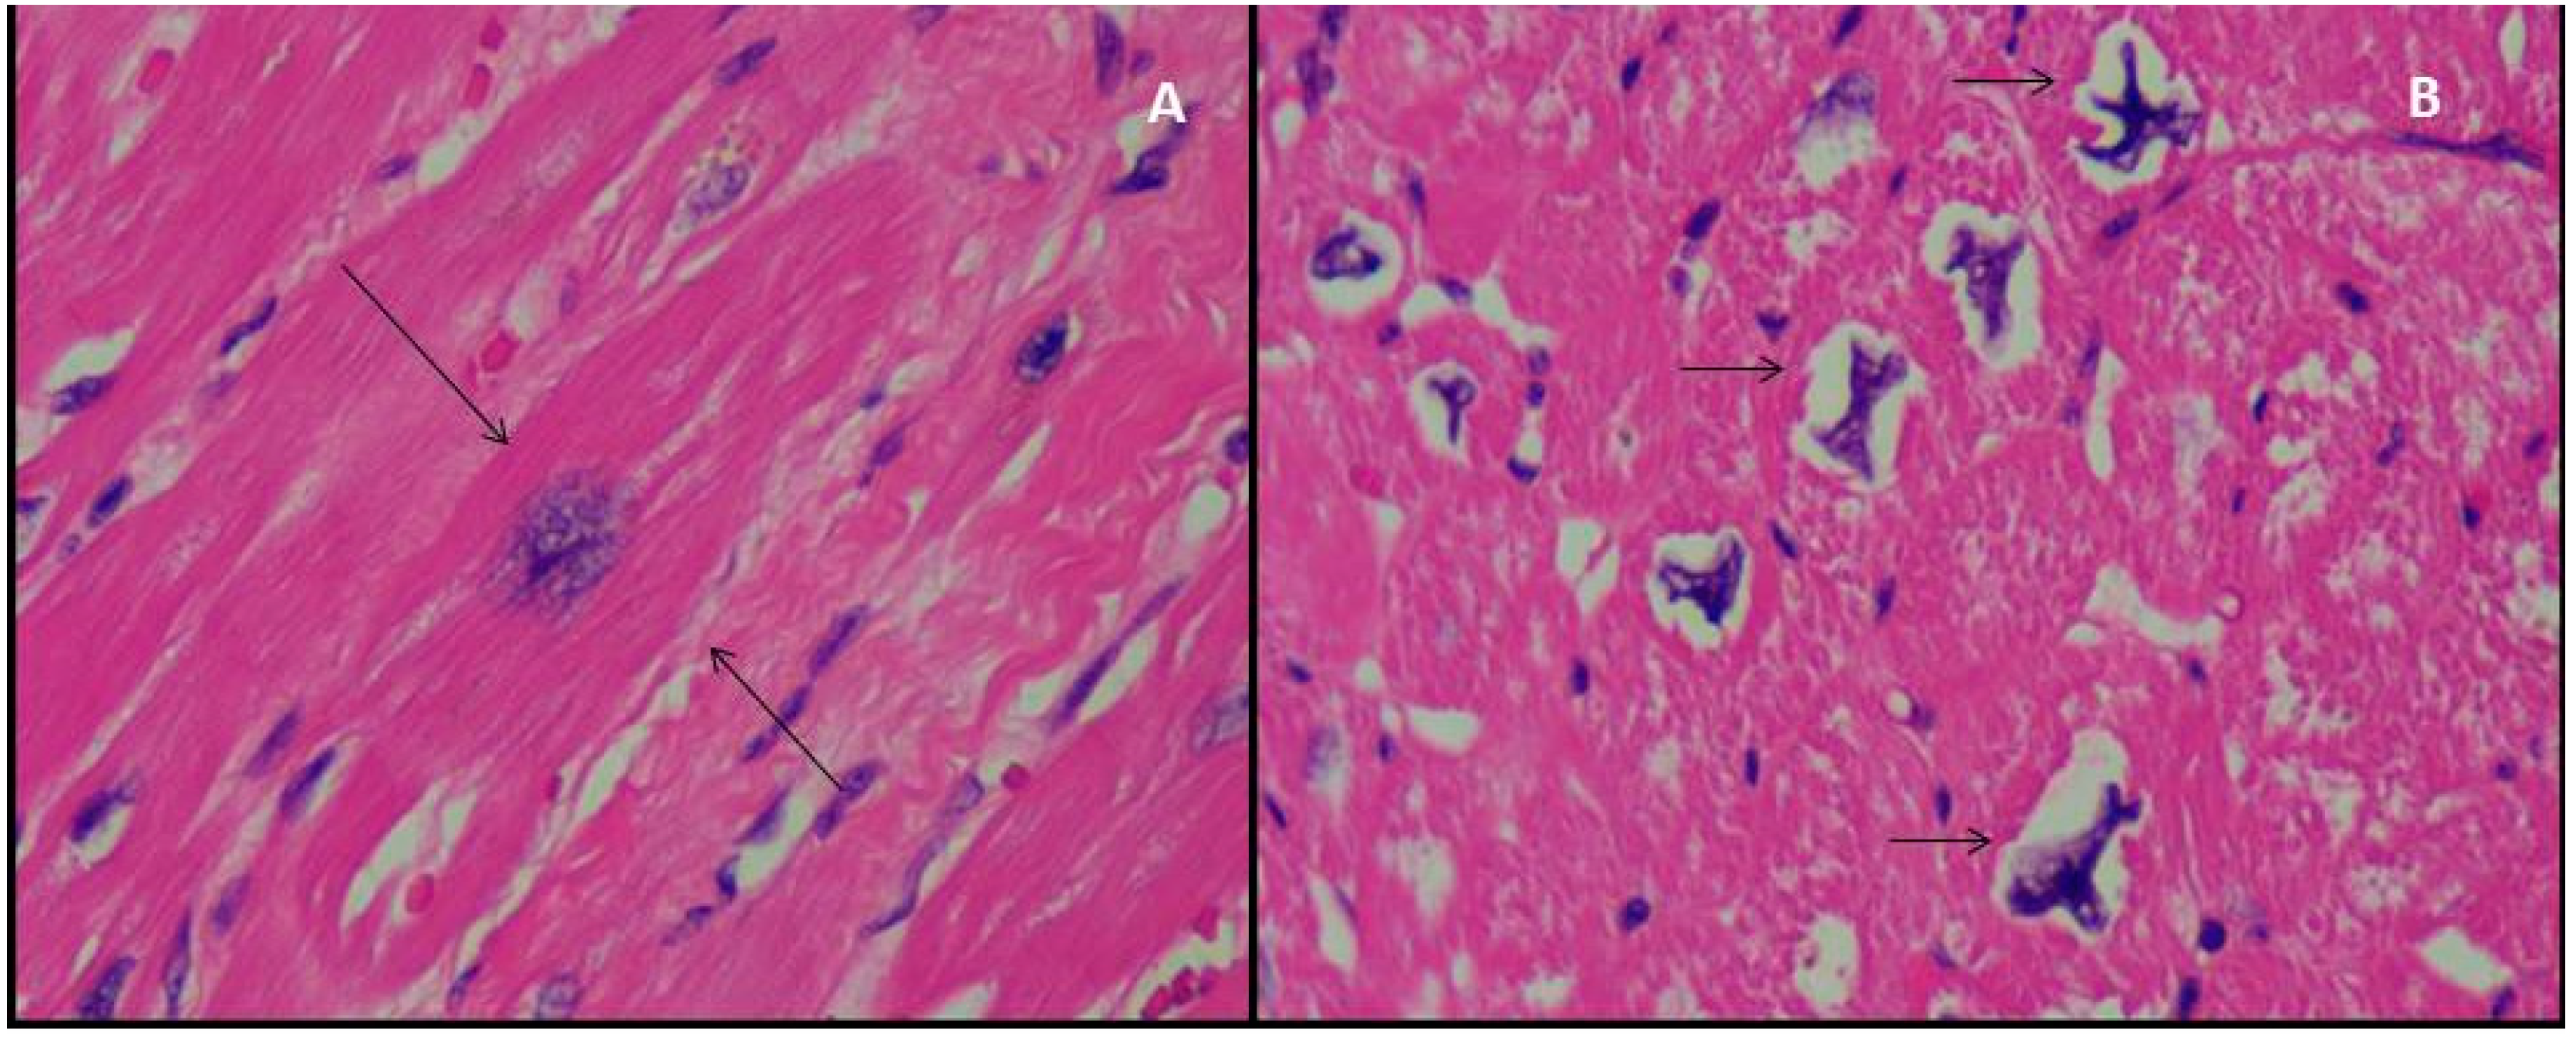

3.2. Anatomopathological Evaluation

- Gerger, D.; Stöllberger, C.; Grassberger, M.; Gerecke, B.; Andresen, H.; Engberding, R.; Finsterer, J. Pathomorphologic findings in left ventricular hypertrabeculation/noncompaction of adults in relation to neuromuscular disorders. Int. J. Cardiol. 2013, 169, 249–253. [Google Scholar] [CrossRef]

- Finsterer, J.; Stollberger, C.; Feichtinger, H. Histological appearance of left ventricular hypertrabeculation/noncompaction. Cardiology 2002, 98, 162–164. [Google Scholar] [CrossRef]